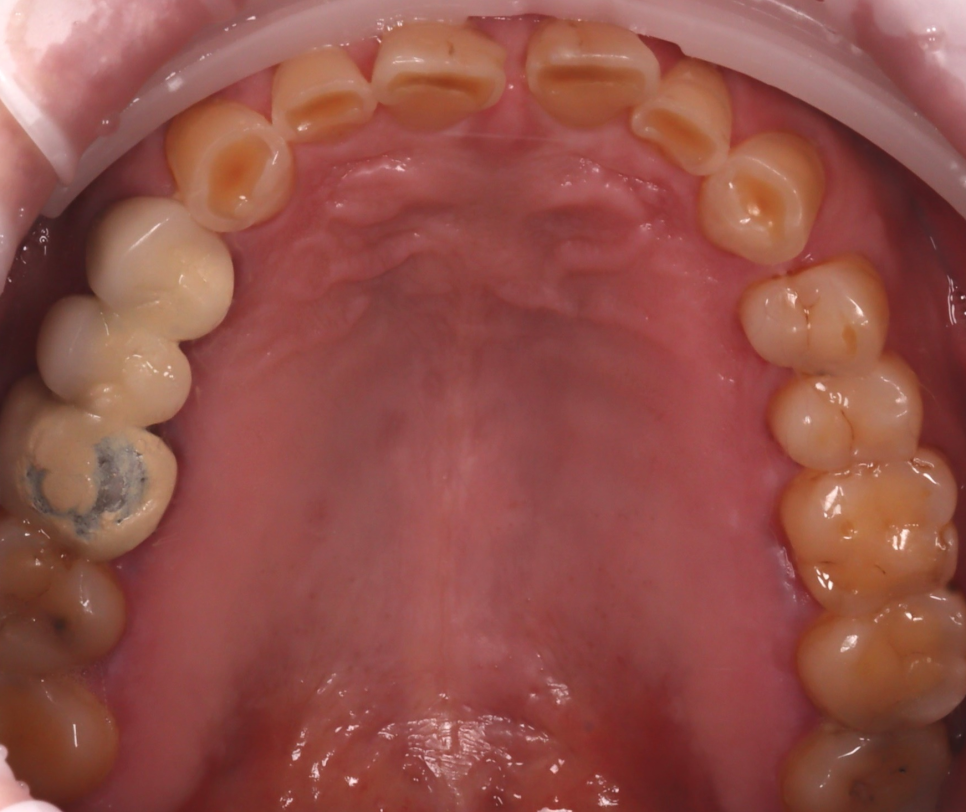

촬영일 : 251013

또, 아랫니가 많이 닳아있어 깊게 무는 형태인 'Deep bite(딥바이트)' 라고 부르는 과개교합 상태였죠.

오랜 시간 서로 부딪히며 위아래가 서로를 갈아버린 흔적이죠.

양쪽 작은 어금니 쪽에는 잇몸 가까이 패인 마모 부위도 있었고 찬물이나 칫솔질 때 "시큰시큰하다"라고 하셨어요.